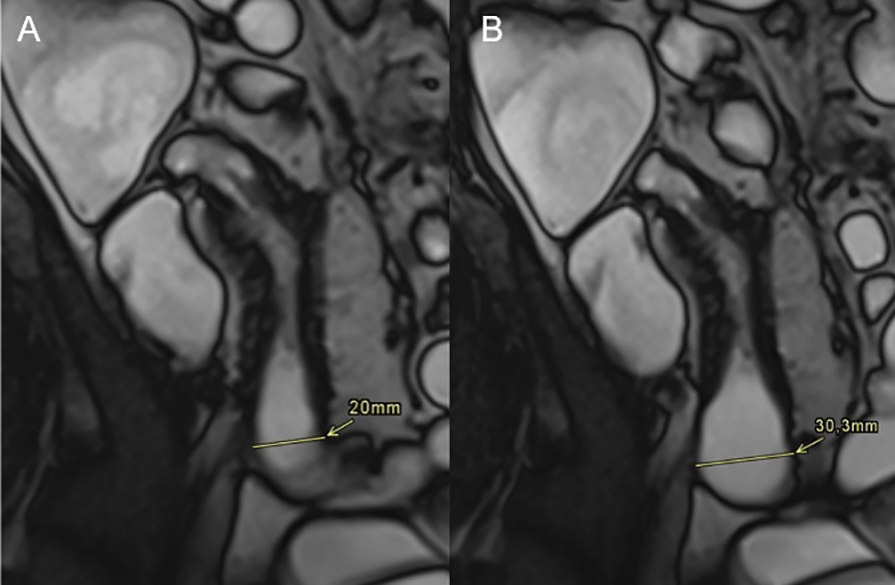

Recent advances in the field focus on functional and quantitative imaging. Cine MRI enables quantification of bowel motility, providing a functional biomarker for inflammation and treatment response [3, 4]. In daily clinical practice, motility sequences are also highly valuable for the early detection of small bowel strictures, as prestenotic dilatation may remain undetected on conventional static MRE images (Figure 3). Texture analysis and radiomics are being investigated for their potential in fibrosis quantification and outcome prediction. In parallel, artificial intelligence may enhance image interpretation, reduce interobserver variability, and support clinical decision‑making [5]. Finally, molecular imaging, including PET‑CT/PET‑MRI and novel tracers, offers the prospect of non‑invasive, quantitative assessment of intestinal inflammation and fibrosis at the molecular level [6].

Figure 3

A 44‑year‑old male with Crohn’s disease in the terminal ileum. (A) Coronal T2 TRUFI image shows prestenotic dilatation of 20 mm, below the threshold for a definite stricture (≥30 mm). (B) A single frame from a CINE sequence demonstrates maximal distension of 30 mm, confirming stricturing Crohn’s disease.